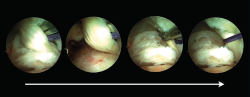

Los portales endoscópicos posteriores de tobillo (posteromedial y posterolateral) se localizan al mismo nivel de la punta del peroné o ligeramente distales a ambos lados del tendón de Aquiles. Se utiliza el portal posterolateral como portal de la visión y el portal posteromedial como portal de trabajo. La técnica endoscópica sigue inicialmente los pasos descritos por Van Dijk(10). La fascia de Rouviere y Canela debe abrirse para acceder a las estructuras de la región posterior del tobillo. Es importante que durante la creación del área de trabajo, la fascia de Rouviere y Canela se abra hacia proximal con el objetivo de evitar la flexión del tendón del FHL cuando este sea transferido hacia el calcáneo. Después de crear un área de trabajo, se identifican las estructuras anatómicas del tobillo a nivel de su región posterior (Figura 1). El tendón del músculo FHL es la principal referencia endoscópica, marcando el límite de seguridad de la zona de trabajo, ya que el paquete neurovascular tibial está situado justo medial al tendón FHL.

Figura 1. Tobillo izquierdo. Visión endoscópica de la región posterior del tobillo (imagen izquierda). 1: tendón del flexor hallucis longus (FHL); 2: proceso posterior del astrágalo (Stieda); 3: articulación subastragalina. Redirigiendo el artroscopio y su visión hacia posterior puede observarse (imagen de la derecha) el tubérculo posterior del calcáneo (4) y la cara anterior del tendón calcáneo (5).